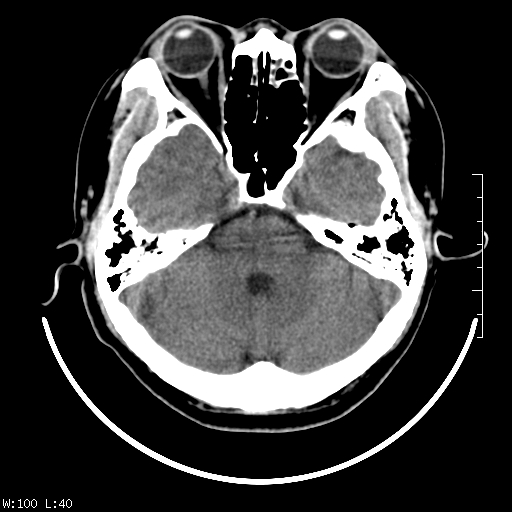

标题: CT22236:男,45,经常头痛。看看脑干正常吗? [打印本页]

标题: CT22236:男,45,经常头痛。看看脑干正常吗?

未见明显异常,建议ct增强或mri检查。

没见异常密度及形态改变啊,我认为是正常的。

颅脑ct轴位平扫颅内未见明确异常。

颅脑ct平扫未见明确异常,必要时mri检查。

颅脑ct平扫未见异常